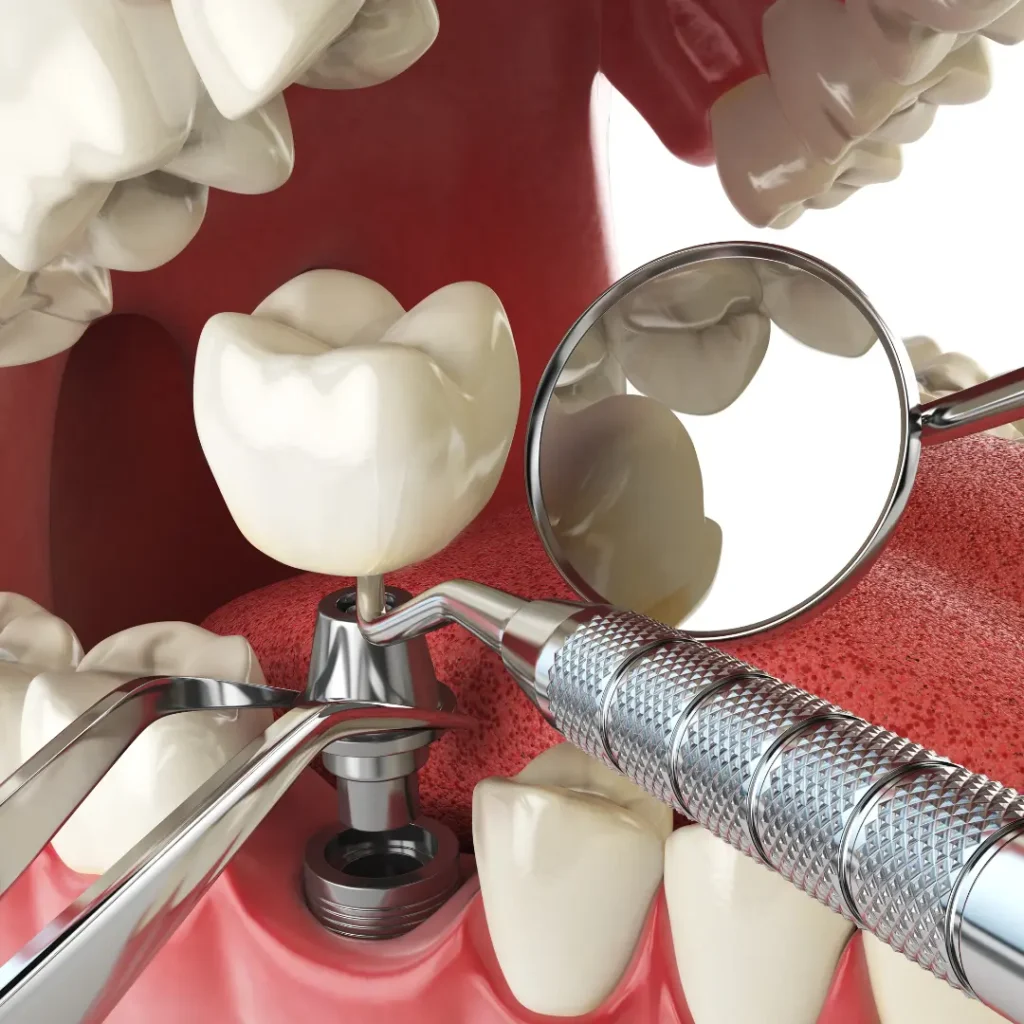

Emergency Dental Implant Services We Offer:

- Same-Day Emergency Dental Implants

- Implant Repairs & Replacements

- Loose or Broken Implant Treatment

- Emergency Extraction + Immediate Implant Options

Common Dental Implant Emergencies We Treat

Cracked or fractured implants

Loose or shifting dental implants

The implant crown fell off or broke

Infection or pain around an implant

Trauma-related tooth loss needs immediate implants